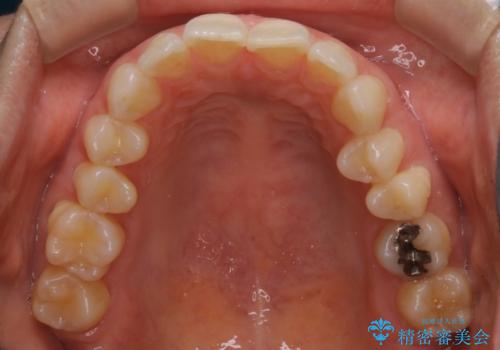

- 下の前歯のがたつきが気になるとの事でご相談にいらした患者様です。

元々はリンガルブラケットをご希望されていましたが、モニター制度を利用してインビザラインによる治療を行いました。

インビザラインFULLで奥歯の噛み合わせから改善させることで、上下の真ん中位置をしっかり合わせることが出来ました。

横顔のシルエットも改善させることができ、大変喜んでいただけました。